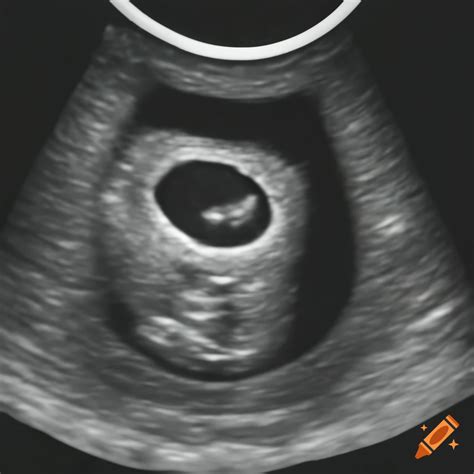

At 6 weeks, the embryo is still very small, measuring about 4-5 millimeters in length. The 6-week sonogram pictures will reveal several key features:

• Gestational Sac: This is the first structure visible on the ultrasound, appearing as a small, fluid-filled sac within the uterus.

• Yolk Sac: A small, round structure within the gestational sac that provides early nutrition to the embryo.

• Embryo: The actual embryo, which may be visible as a tiny, curved structure within the gestational sac.

• Fetal Pole: A thickened area within the embryo that will eventually develop into the fetus.

• Heartbeat: In some cases, a flickering heartbeat may be visible, indicating that the embryo is developing normally.

• Normal Findings: Clear visualization of the gestational sac, yolk sac, and embryo with a detectable heartbeat.

• Inconclusive Findings: The embryo may not be clearly visible, or the heartbeat may not be detected. This can happen if the embryo is positioned in a way that makes it difficult to see.

• Abnormal Findings: In some cases, the ultrasound may reveal abnormalities such as an empty gestational sac (anembryonic pregnancy) or an ectopic pregnancy, where the embryo implants outside the uterus.